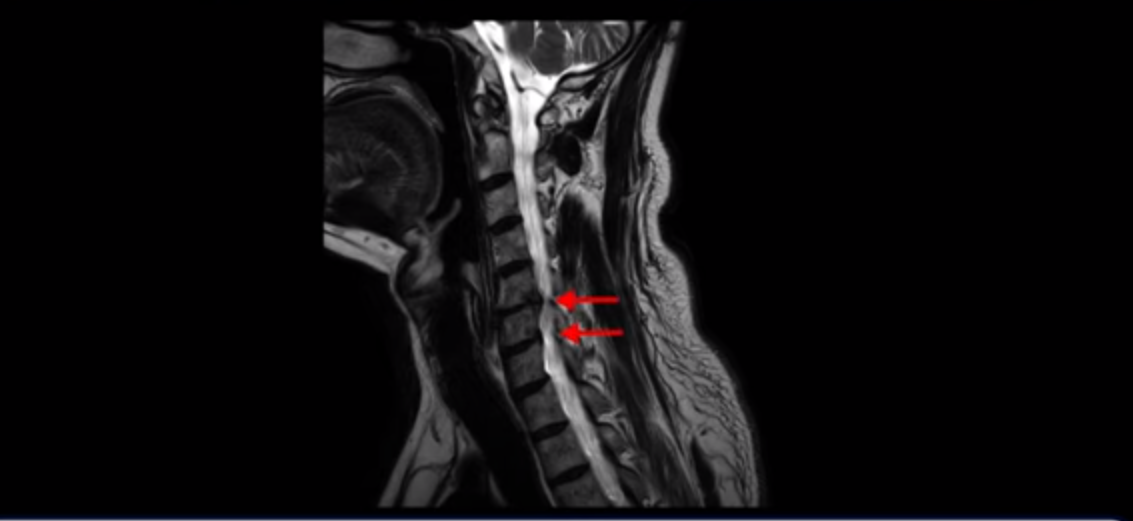

우선 이분 증상은 좌측 어깨와 팔 통증입니다. 이분 MRI를 보면 5번 6번과 6번 7번이 안 좋아 보입니다.

5번 6번에는 오른쪽과 왼쪽 모두 디스크 파열이 있고,

6번 7번에는 왼쪽으로 디스크가 밀려 나와 있습니다.

왼쪽으로 신경이 빠져나가는 추간공을 보면 보시다시피 5번 6번과 6번 7번 신경 구멍이 아래나 위에 비해 막혀있는 게 보입니다.

디스크도 밀려 나와 있고 협착도 있는 겁니다.

이분 왼쪽 어깨와 팔 통증이 갑자기 생긴 이유는 5번 6번 디스크 또는 6번 7번 디스크가 갑자기 밀려 나온 것이 원인일 것으로 보이는데, 그럼 이 디스크들이 밀려 나와서 신경을 자극하거나 누르는데 어떻게 이게 수술 없이도 좋아질 수 있는 걸까요?